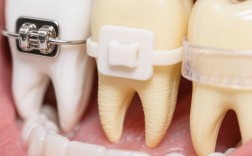

| 传统金属托槽矫正 | 在牙齿表面粘贴金属托槽,通过弓丝与结扎丝施加力 | 性价比高、适用范围广、控根移动精确 | 美观性差、舒适度较低、口腔清洁难度大 | 牙齿严重拥挤、骨性错颌等复杂病例 |

| 自锁托槽矫正 | 托槽自带闭锁结构,减少弓丝与托槽的摩擦力,提升矫正效率 | 矫正周期缩短(约20%-30%)、复诊间隔延长、疼痛感轻 | 费用略高于传统矫正、托槽体积较大 | 对疼痛敏感、希望缩短矫正时间的患者 |